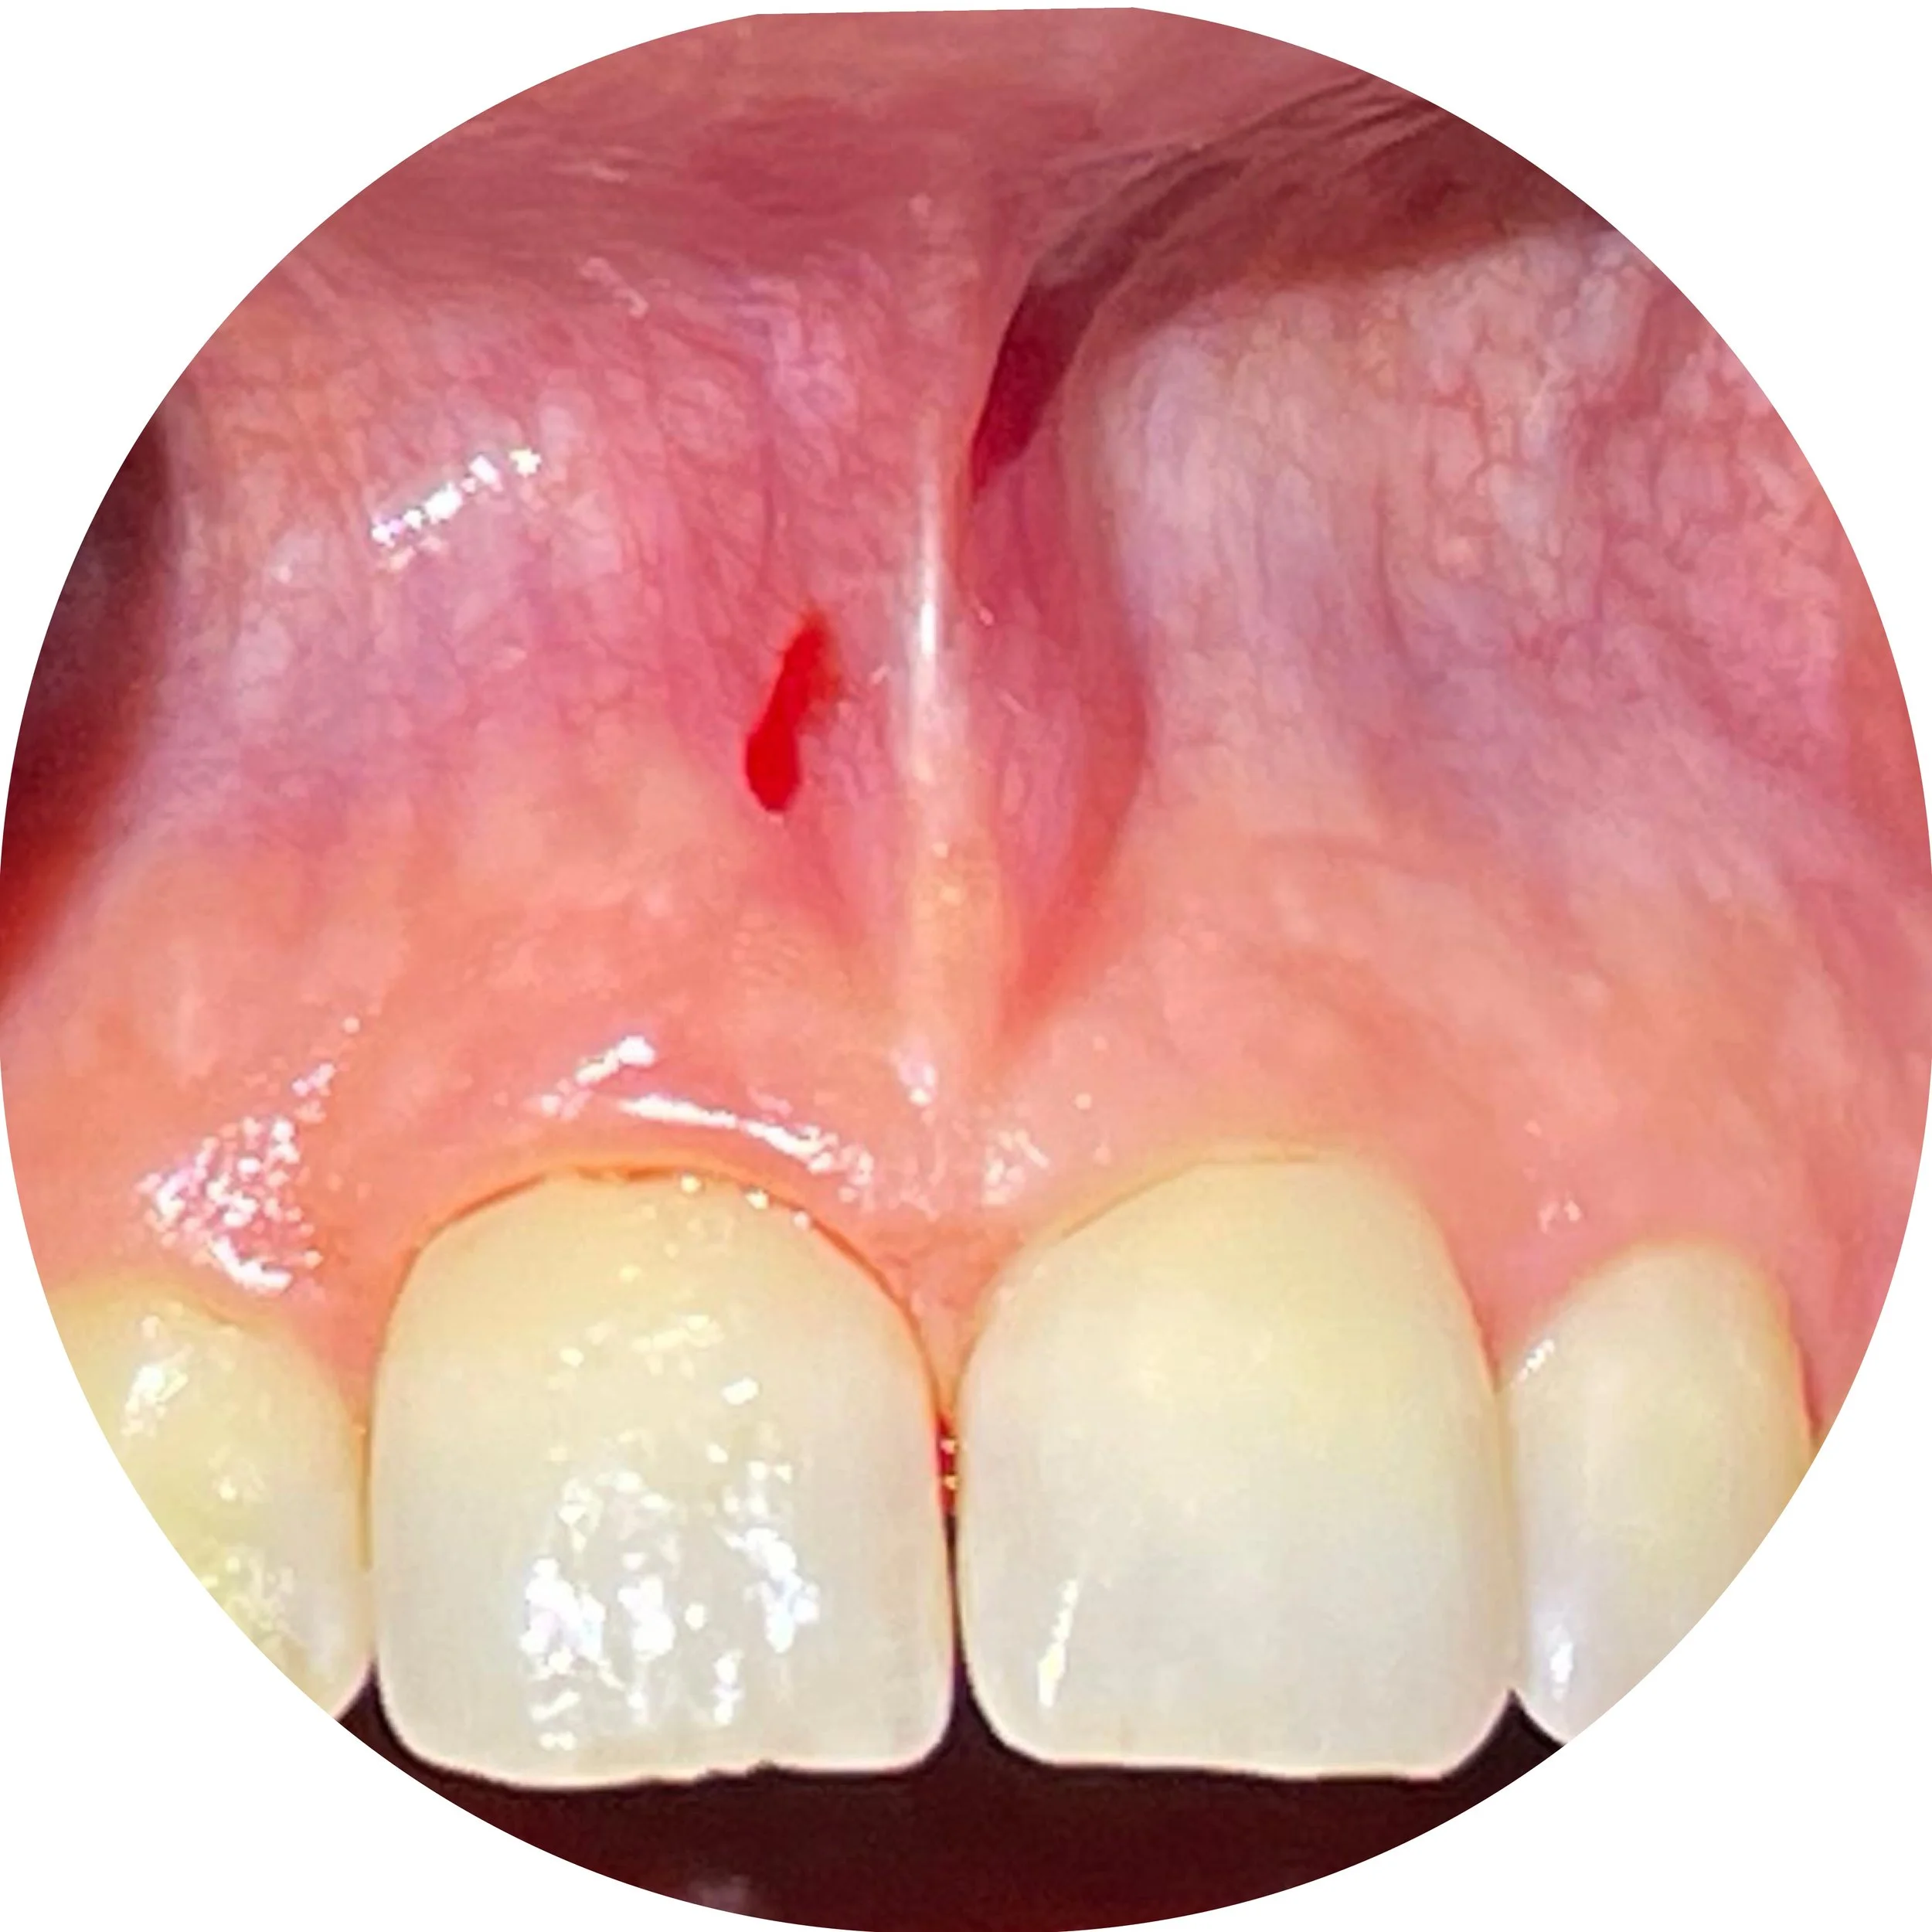

This patient came to our office and mentioned that her upper lip was too high

She was concerned that this was effecting her appearance and speech. It was also making her a mouth breather. These issues were related to the fact that she could not close her lips. We cut the labial (lip) frenulum with a our LightScalpel CO2 laser with minimal bleeding and sutured. The patient noticed she could close her lips much easier.

Close-up photograph of the inside of a human mouth showing teeth and the soft palate, with a small cut or lesion on the soft palate.